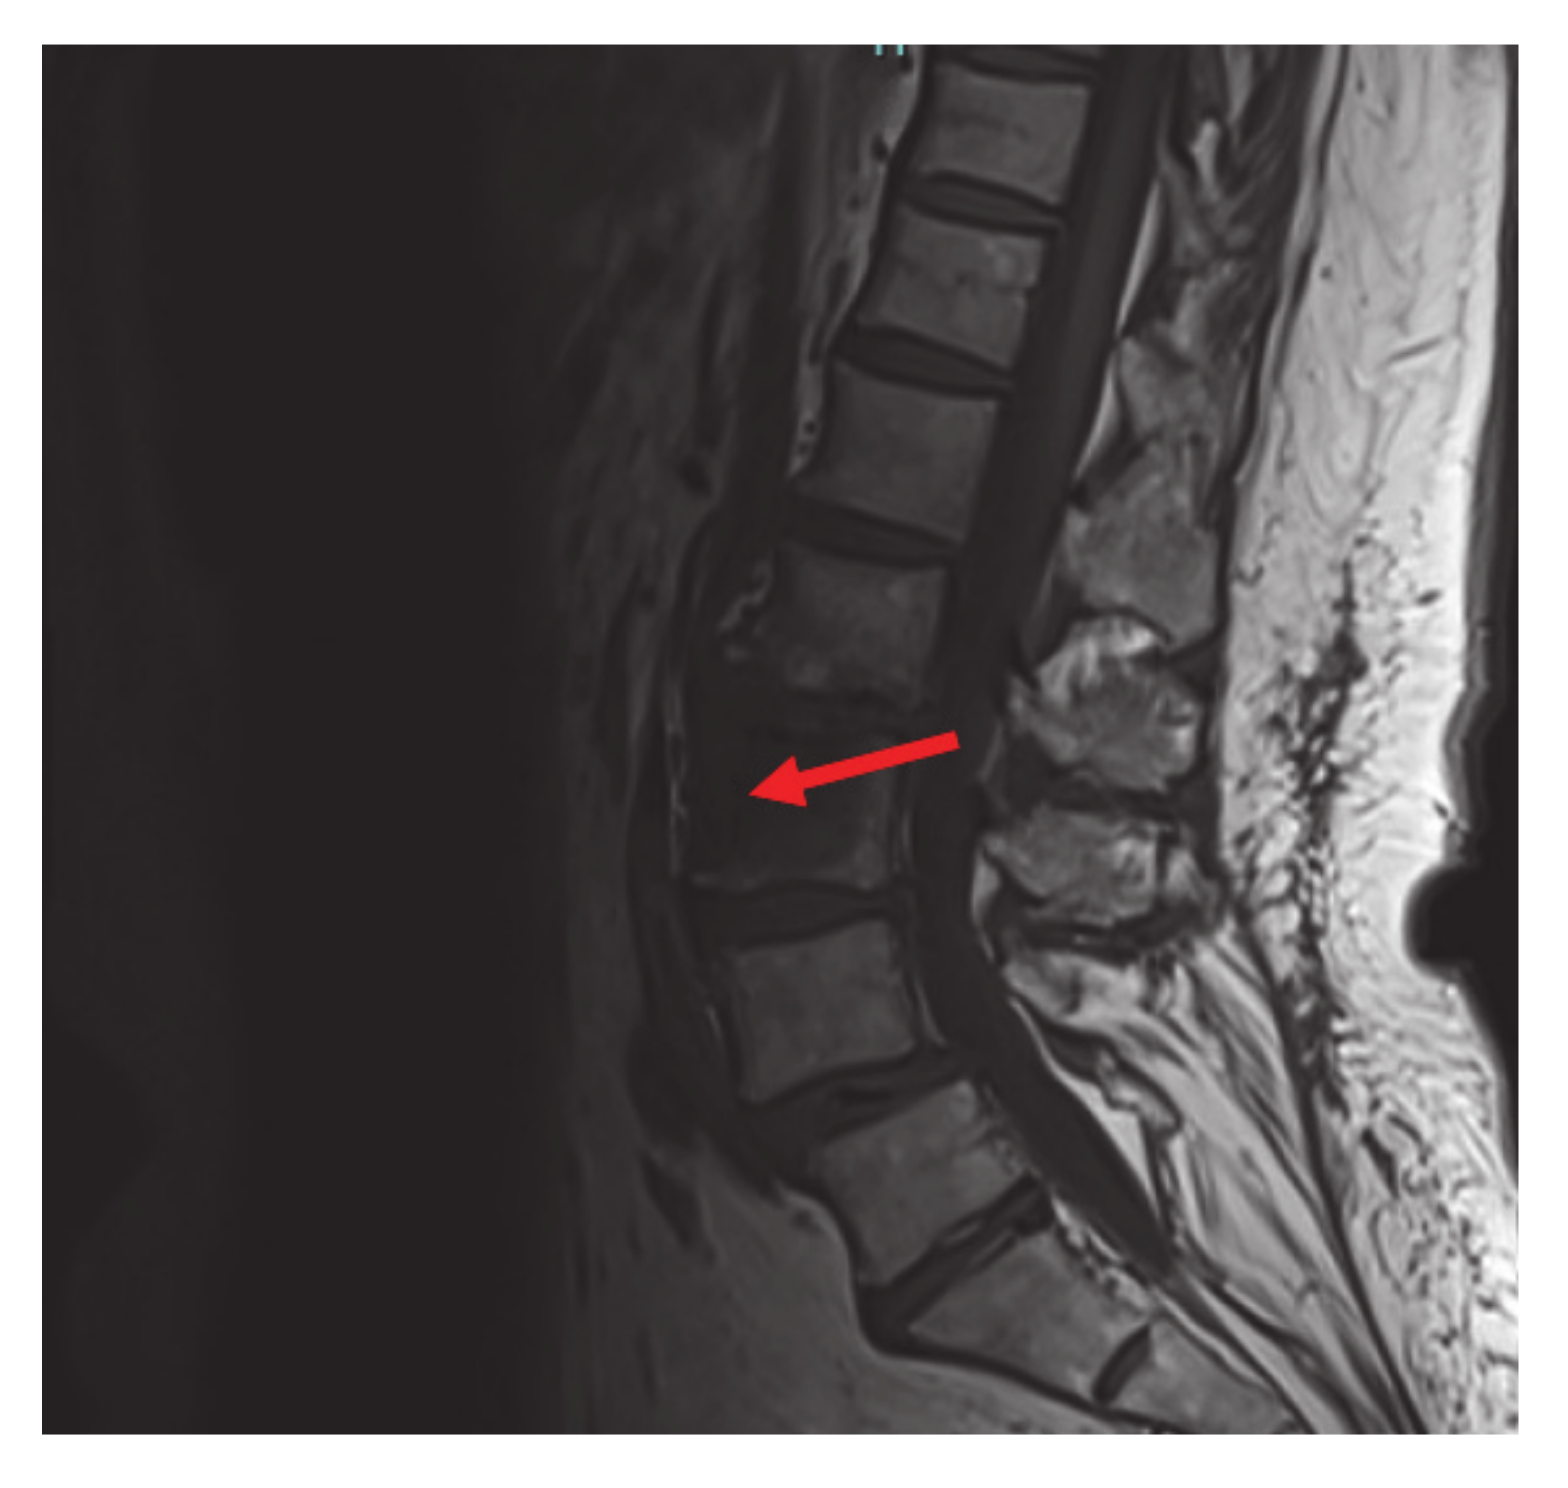

The mutation detected is different from the more common V600 mutation and is an extremely rare variant of a non-V600 mutation. Non-V600 mutations are not usually seen in non-smokers, which makes this case more unusual. The patient was referred for palliative left hip and pelvic radiation with plans to start RAF and MEK inhibitors dabrafenib and trametinib after completion of radiation therapy. Guardant 360 confirmed the BRAF pT599dup mutation. Following completion of radiation to the hip, her pain was significantly improved, and she was started on dabrafenib/trametinib, only complaining of mild nausea that responded to anti-emetics. The patient also had an Magnetic Resonance Imaging (MRI) of cervical, thoracic, and lumbar spine done that showed an L3 vertebral body metastasis without compression deformity or canal compromise and severe facet arthropathy with grade one anterolisthesis of L4 on L5 (Figure 3).

Figure 3.

Magnetic Resonance Imaging (MRI) lumbar spine: L3 vertebral body metastasis (red arrow) without compression deformity or canal compromise. Not visualized, severe facet arthropathy with grade 1 anterolisthesis of L4 on L5.